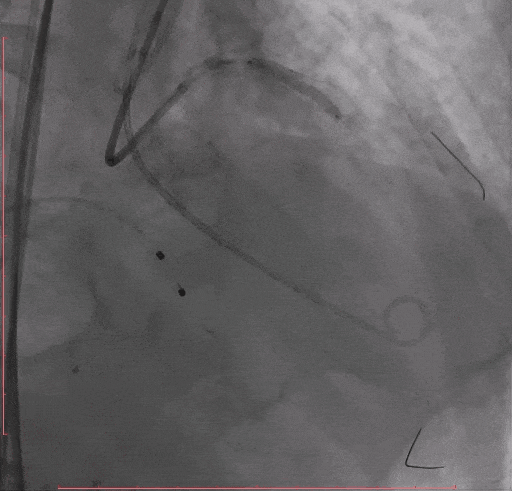

Step 4 旋磨后予以前降支支架植入

Step 5 左主干植入支架 回旋支开口予以切割+药物球囊